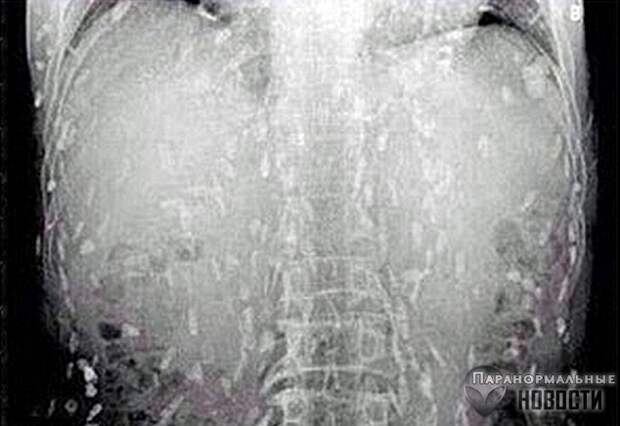

Житель провинции Гуандун обратился в больницу с жалобами на боли в животе - и рентген показал, что все его органы буквально оккупированы червями-солитерами.

Врачи считают,что причиной этого стало увлечение мужчины суши, он постоянно ел их с сырой рыбой. Червей в его организме было так много, что первым его порывом, когда он увидел на рентгене копошащуюся армию паразитов внутри себя, было сигануть из окна. Его успели остановить.